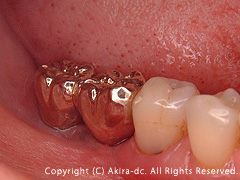

術前写真です。(右下奥歯抜歯後) |

上部構造・土台装着前になります。 |

土台(アバットメント)の装着です。 |

上部構造の装着した状態です。 |